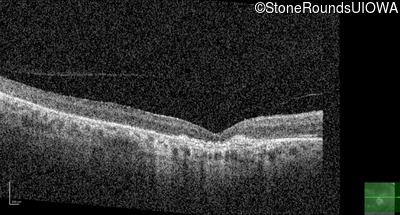

Optical Coherence Tomography - Left - 20/80

Exemplar / OCT Stack